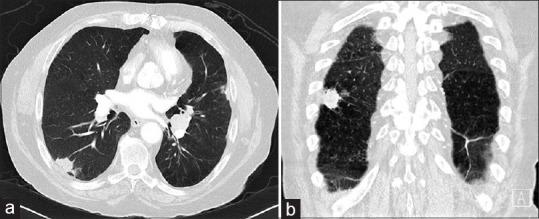

We present a case of lung cancer incidentally detected as a pulmonary nodule on computed tomography attenuation correction (CTAC) images during myocardial perfusion scintigraphy (MPS). Unfortunately, the incidental lesion was not fully investigated following MPS report and had developed into metastatic lung carcinoma when diagnosed over 1 year later, with failure of subsequent emergent chemotherapy. The disease appeared to be localized when initially detected during MPS. This case highlights the importance and potential clinical value of routine review of CTAC images in MPS with appropriate reporting and further investigation of suspicious incidental findings. In addition, the importance of effective communication between nuclear medicine department and treating team is clear to ensure suspicious incidental findings are given sufficient credence and thoroughly investigated promptly to avoid adverse clinical outcomes.

我们报告一例在心肌灌注闪烁扫描(MPS)期间通过计算机断层扫描衰减校正(CTAC)图像偶然发现为肺结节的肺癌病例。不幸的是,MPS报告后未对该偶然发现的病变进行充分检查,1年多后确诊时已发展为转移性肺癌,随后的紧急化疗失败。该疾病在MPS最初检测时似乎局限于局部。本病例强调了在MPS中对CTAC图像进行常规复查并进行适当报告以及对可疑偶然发现进行进一步调查的重要性和潜在临床价值。此外,核医学科与治疗团队之间有效沟通的重要性显而易见,以确保可疑偶然发现得到充分重视并及时进行彻底调查,避免不良临床后果。